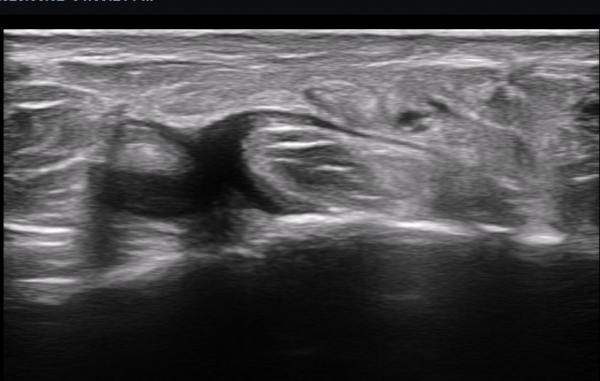

ºñº¹½Å°æ Á¾´Ü¸é°Ë»ç(»çÁø 14, 15)¿¡¼­ ºñº¹½Å°æÀÇ Àü¹ÝÀûÀÎ Àú¿¡ÄÚ ºÎÁ¾°ú ºñº¹½Å°æ ½ÉÃþÀ¸·Î ´Üºñ°ñ°Ç³»

³¶Á¾¼º º¯º¯ÀÌ °üÂûµÈ´Ù.